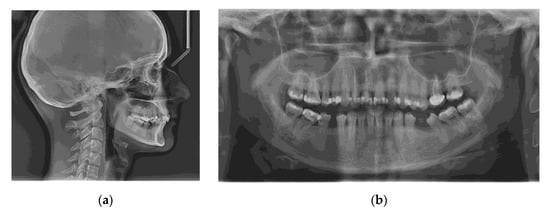

To calculate the amount of performed molar intrusion, the difference of the linear distance from the mesiobuccal cusp of the maxillary first molar to a custom palatal plane (CPP) was measured on CBCT images before and after intrusion mechanics. The CPP was defined by the following three points: ANS, and the lowest points of the pterygoid hamulus on the left and right sides. The measurements were performed by one maxillofacial surgeon and one orthodontist, twice, and mean values were considered (Table 4).

Table 4.

The CBCT measurements before and after intrusion at the level of upper first molar and upper first premolar.

The measurement method is shown in Figure 7.

Figure 7.

Intrusion amount, at the level of the mesiobuccal cusp of the right upper first molar (the distance between the cusp tip and CPP): (a) before intrusion: 23.76 mm; (b) after intrusion: 20.31 mm.

Elastomeric chains were changed every four weeks. Approximately 3.59 mm of intrusion was achieved on the right buccal side and 2.21 mm on the right palatal side in six months, 2.26 mm on the left buccal side, and 1.86 mm on the left palatal side in nine months. After intrusion, ligature stainless steel wires were used to keep the intruded teeth in place. Subsequently, upper and lower teeth were included in a full arch appliance, with a 0.022 MBT prescription.